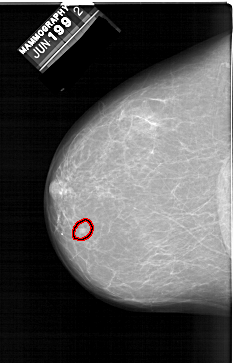

A_1398_1.LEFT_MLO

FILE: A_1398_1.LEFT_MLO.OVERLAY

TOTAL_ABNORMALITIES 1

ABNORMALITY 1

LESION_TYPE MASS SHAPE LOBULATED MARGINS CIRCUMSCRIBED

ASSESSMENT 3

SUBTLETY 3

PATHOLOGY BENIGN

TOTAL_OUTLINES 1

BOUNDARY